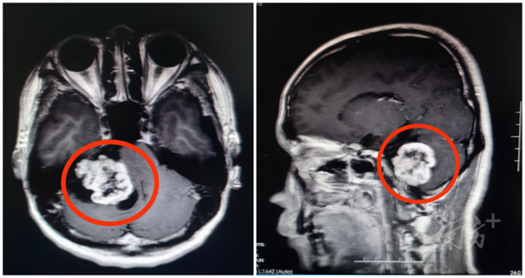

“从影像资料来看,怀疑是听神经瘤的可能性比较大。”广东三九脑科医院副院长鲁明接诊时发现,一个鸡蛋大小的肿瘤正压着患者的内听道和脑干,除了肢体乏力、面肌痉挛、头痛等症状外,还严重影响了患者的听力。

患者术前影像资料,图中圈出来的为听神经瘤。